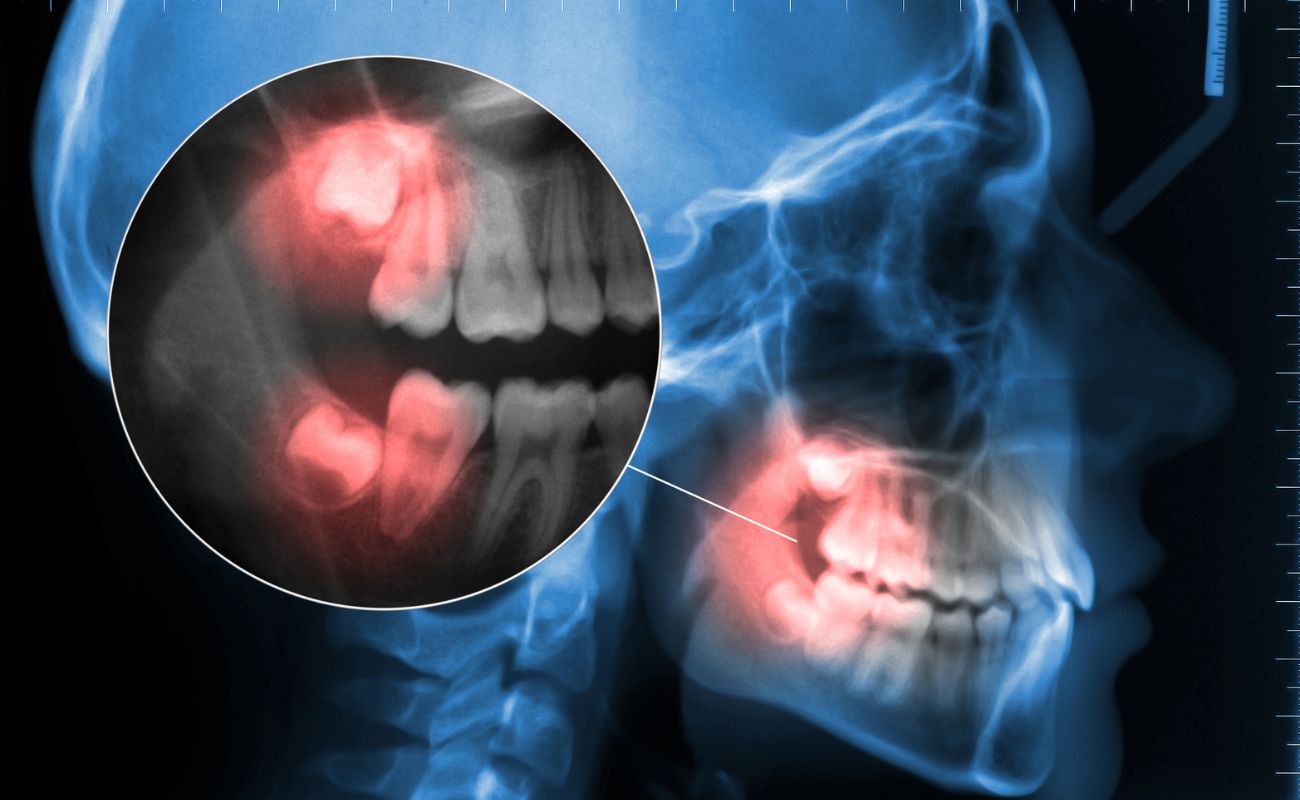

Cómo se Diagnostica la Necesidad de una Extracción de Muelas del Juicio

El diagnóstico para la extracción de muelas del juicio comienza con un examen dental completo y una radiografía para evaluar la posición y el desarrollo de las muelas. El dentista revisará:

- Posición de las muelas del juicio en relación con los otros dientes.

- Signos de infección o daño a los dientes cercanos.

- Presencia de quistes o problemas con la estructura ósea.

Basado en esta evaluación, el dentista determinará si la extracción es la mejor opción.